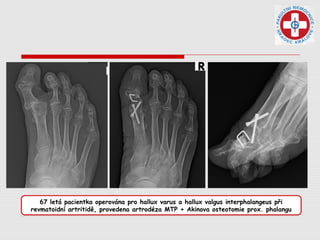

67 letá pacientka operována pro hallux varus a hallux valgus interphalangeus při

revmatoidní artritidě, provedena artrodéza MTP + Akinova osteotomie prox. phalangu